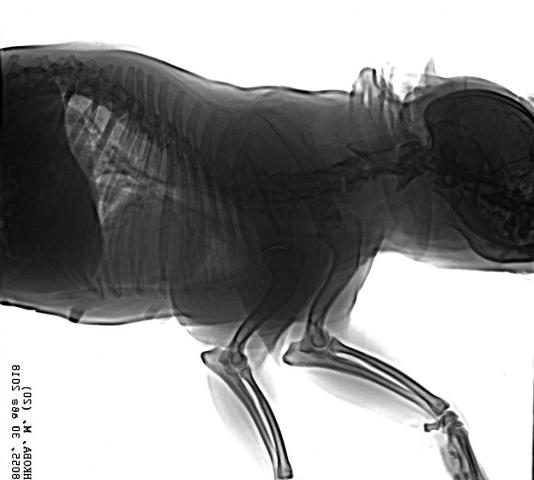

Французский бульдог,6 лет.Стала плохо ходить,что- то с позвоночником.Врачи не могут поставить диагноз.Есть снимки.Помогите!

Снимки хорошие, качественные, но совершенно не информативные. На этих пленках патология не определяется. Но здесь нет снимка, который нужен обязательно - поясничный отдел позвоночника в прямой проекции (такой, как 3-й, но только не шея, а поясница).

Нет,наоборот.Собака сначала стала немного наклонять голову вправо.Когда были на консультации у окулиста,то он обратил внимание на это ,сказал,что есть какие-то изменения в области шеи.Я отсутствовала дома 2 недели.Приехала,собаку вообще не узнала.Крен головы вправо стал еще сильнее,передние ноги как-то ослабли.Она идет,может споткнуться,упасть.Сходили,сделали рентген.снимок.Поставили диагноз:атланто-аксиальная нестабильность шейного отдела,спондилоартроз. Проколола 5 дней:актовегин,папаверин,комбилипн,мидокалм,дексаметазон. Пока делала уколы и еще дней 5 после этого собаке стало легче,а потом опять вернулись к тому, что было.На консультации врач сказал,что дальше просто колоть преднизалон. Я уехала к другому врачу,тот сделал снимки,которые я Вам отослала.Сказал, что диагноз не подтверждает,на пальцах показал, что со спинным мозгом все нормально.С помощью какой-то процедуры (бумаги на работе)обнаружил перфорацию барабанной перепонки.Выписал лечение:цефтриаксон,циклоферон,цебролизин(колола 2 дня,стало хуже),комбилипен.В уши-изотик.Сказал,что может быть у собаки был инсульт.Собаке от лечения хуже.Вот такие дела.